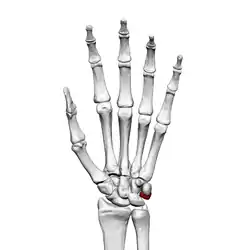

Triquetral bone

The triquetral bone (/traɪˈkwɛtrəl, -ˈkwiː-/; also called triquetrum, pyramidal, three-faced, and formerly cuneiform bone) is located in the wrist on the medial side of the proximal row of the carpus between the lunate and pisiform bones. It is on the ulnar side of the hand, but does not directly articulate with the ulna. Instead, it is connected to and articulates with the ulna through the Triangular fibrocartilage disc[1] and ligament, which forms part of the ulnocarpal joint capsule.[2] It connects with the pisiform, hamate, and lunate bones. It is the 2nd most commonly fractured carpal bone.

The triquetral is one of the eight carpal bones of the hand. It is a three-faced bone found within the proximal row of carpal bones. Situated beneath the pisiform, it is one of the carpal bones that form the carpal arch, within which lies the carpal tunnel. [3]: 708

The triquetral bone may be distinguished by its pyramidal shape, and by an oval isolated facet for articulation with the pisiform bone. It is situated at the upper and ulnar side of the carpus. To facilitate its palpation in an exam, the hand must be radially deviated so that the triquetrium moves out from under the ulnar styloid process. The triquetrum may be difficult to find, since it also lies under the pisiform.